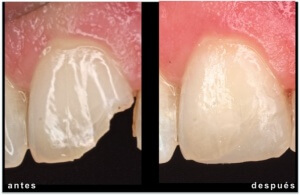

ESTÉTICA REPARACIÓN DE FRACTURA CON COMPOSITE